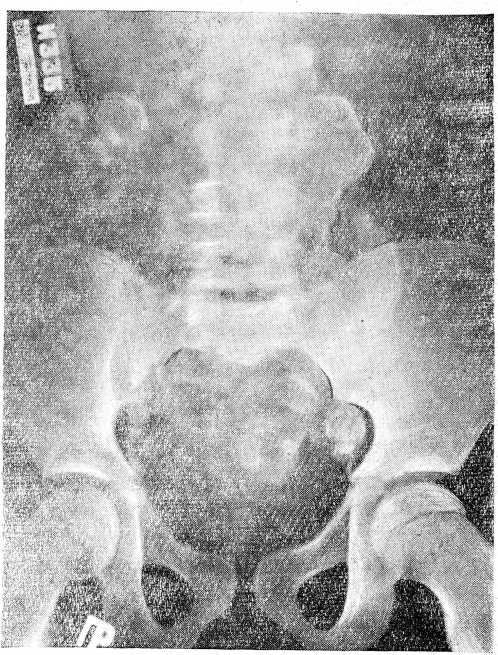

На обзорном снимке пояснично-крестцового отдела позвоночного столба определяются множественные обызвествленные лимфатические узлы раличной величины, расположенные по обеим сторонам позвоночника и в тазу (рис. 1).

Рис.1